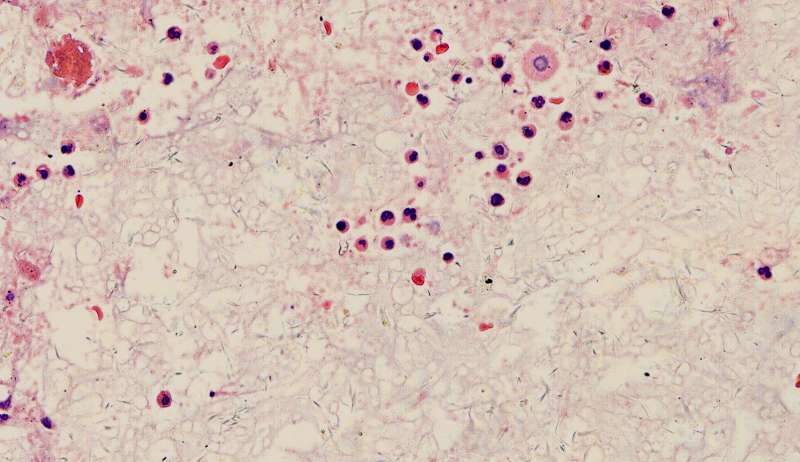

许多小白球--隐球菌,不做PAS及六铵银特染也看得清 荚膜的感觉明显 第三例的CT

这些就是隐球菌,常被巨噬细胞吞噬,大多为多核巨噬细胞 隐球菌感染,在免疫力正常情况下,就是个肉芽肿 小白球,略显淡蓝色,这是荚膜的感觉

隐球菌在HE染色是小白球,隐隐的,球状的。在PAS染色是红色的小球,在六铵银染色是黑褐色的小球。